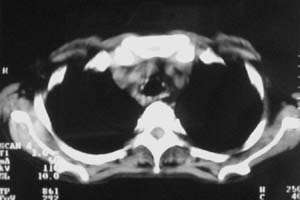

以下是引用zjzjr在2007-9-20 12:29:00的发言:[br]双肺磨玻璃改变,考虑肺水肿.

以下是引用yangzongshan在2007-9-20 18:29:00的发言:[br]两肺毛玻璃样改变,其内可见肺纹理影,无胸腔积液,故考虑肺泡蛋白沉积症

以下是引用276894491在2007-9-20 13:40:00的发言:[br]考虑肺水肿;外源性过敏性肺炎不排除。

以下是引用逸风在2007-9-20 20:45:00的发言:[br]两肺磨玻璃样改变,临床病史短,发热,考虑病毒感染合并右肺代偿性肺气肿.待排肺水肿,病史短,不支持肺泡蛋白沉着症.